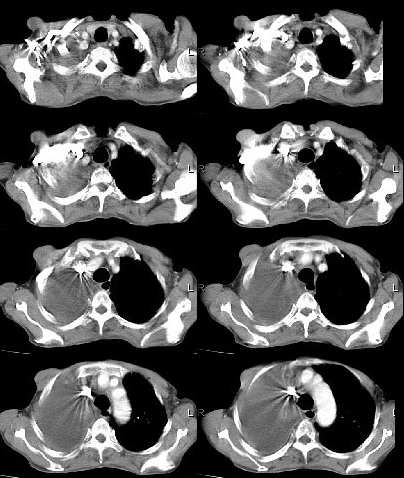

男,76岁,因心累,气紧加重,伴吐白色沫哝痰,偶尔有低烧,无盗汗。{门诊患者未见其它检查}

右肺上叶私有肿块,其内见条状 点状钙化,上叶后段支气管有阻塞征象,纵隔内见淋巴结影,大量胸水,陈旧性结核,肺癌不排除.

病灶在右上叶支气管的后段旁,成类圆形,约2.3厘米大小,其内见钙化密度区,病灶平扫为77,强化为87.左肺上叶尖后段沿血管支气管分布见小结节.我认为右上叶后段支气管开口有截断.我首先考虑是右中央型肺癌伴右恻大量胸腔积液,但左肺的病变我真的有的不好解释,希望各位战友继续讨论,不对之处望指出!!谢谢!!!

右肺毁损萎陷,其内可见钙化灶、残存空腔及支气管影。左上叶可见多发小结节影。纵隔左移,其内未见肿大淋巴结。右侧胸腔大量积液。考虑:肺结核并右肺毁损;右侧胸腔大量积液。

右侧大量胸腔积液伴右肺压迫性肺不张,上叶内是不是结核灶?

右肺萎陷,上叶似有肿块,其内见条状、点状钙化,上叶后段支气管有阻塞征象,纵隔内见肿大淋巴结影,右侧大量胸水,陈旧性结核。同时不排除在原有双肺结核的基础上出现右上肺癌并胸膜及纵隔淋巴转移的可能

支持右肺ca伴胸水,依据1有点状钙化肿块2支气管截断。最好抽胸水后再扫描,支气管镜检最好。

右上叶后段开口处可见约3cm·3cm大小的肿块,边缘较光滑,无明显分叶且有钙化,右上叶支气管后壁受侵不明显,加上左上叶病灶。我首先考虑肺结核,胸腔积液。右肺不张。还是建议支气管镜检查,或者胸水检查。

一看这个病人的定位片大致倾向恶性病变,因胸水漫顶,纵隔少偏.右上肺门旁肿块肯定,肺内肿瘤可能性很大.右上肺病灶多为陈旧性结核.实际上结核病并发肿瘤并非少见.所以二元论诊断也不奇怪.

右后段处示一肿块但无明显肺癌强化方式,其内尚见钙化,胸膜亦无结节样增厚,再加上左肺结核表现(支血束结节样增粗不确切),则更支持结核伴大量胸液表现。